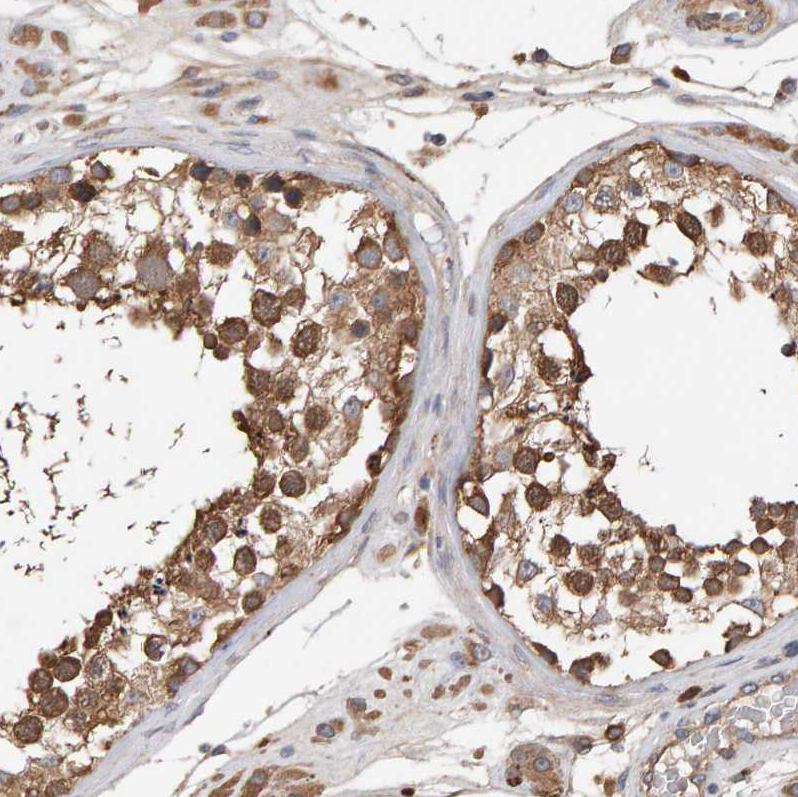

Immunohistochemical staining of human testis shows strong cytoplasmic positivity in cells in seminiferous ducts.